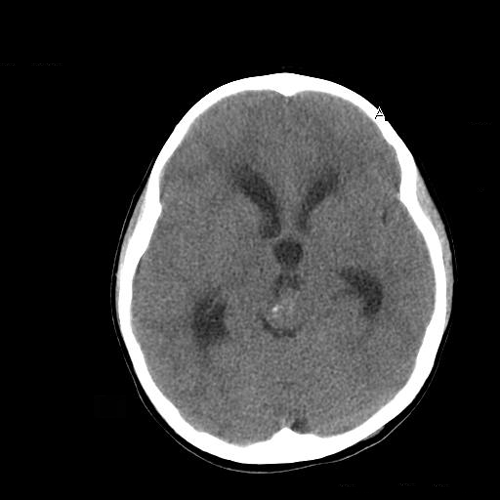

The patient was a 5 year-old Vietnamese boy who presented with the chief complaints of headaches, vomiting, and ataxia.  CT scan revealed a pineal tumor with small calcifications and hydrocephalus (Panel 1).  On MRI, the mass is a well demarcated midline mass involving the pineal area. There is also heterogeneous enhancement and cystic component (Panel 2 and 3).

Laboratory studies reveal elevated alpha-fetoprotein  in both the cerebral spinal fluid (CSF). A clinical diagnosis of primary germ cell tumor was made. The CSF cytology was negative for neoplastic cells. A ventriculoperitoneal shunt was placed to relieve the hydrocephalus and chemotherapy was started. The size of the tumor increased after the chemotherapy and the alpha-fetoprotein level in serum remained elevated. Surgery was performed and yielded multiple fragments of tan, soft tissue, 5.0 x 2.0 x 1.0 cm in aggregate, for examination. On gross examination, neither calcified tissue nor hair were found. The followings are representative histologic images of the excised tumor.